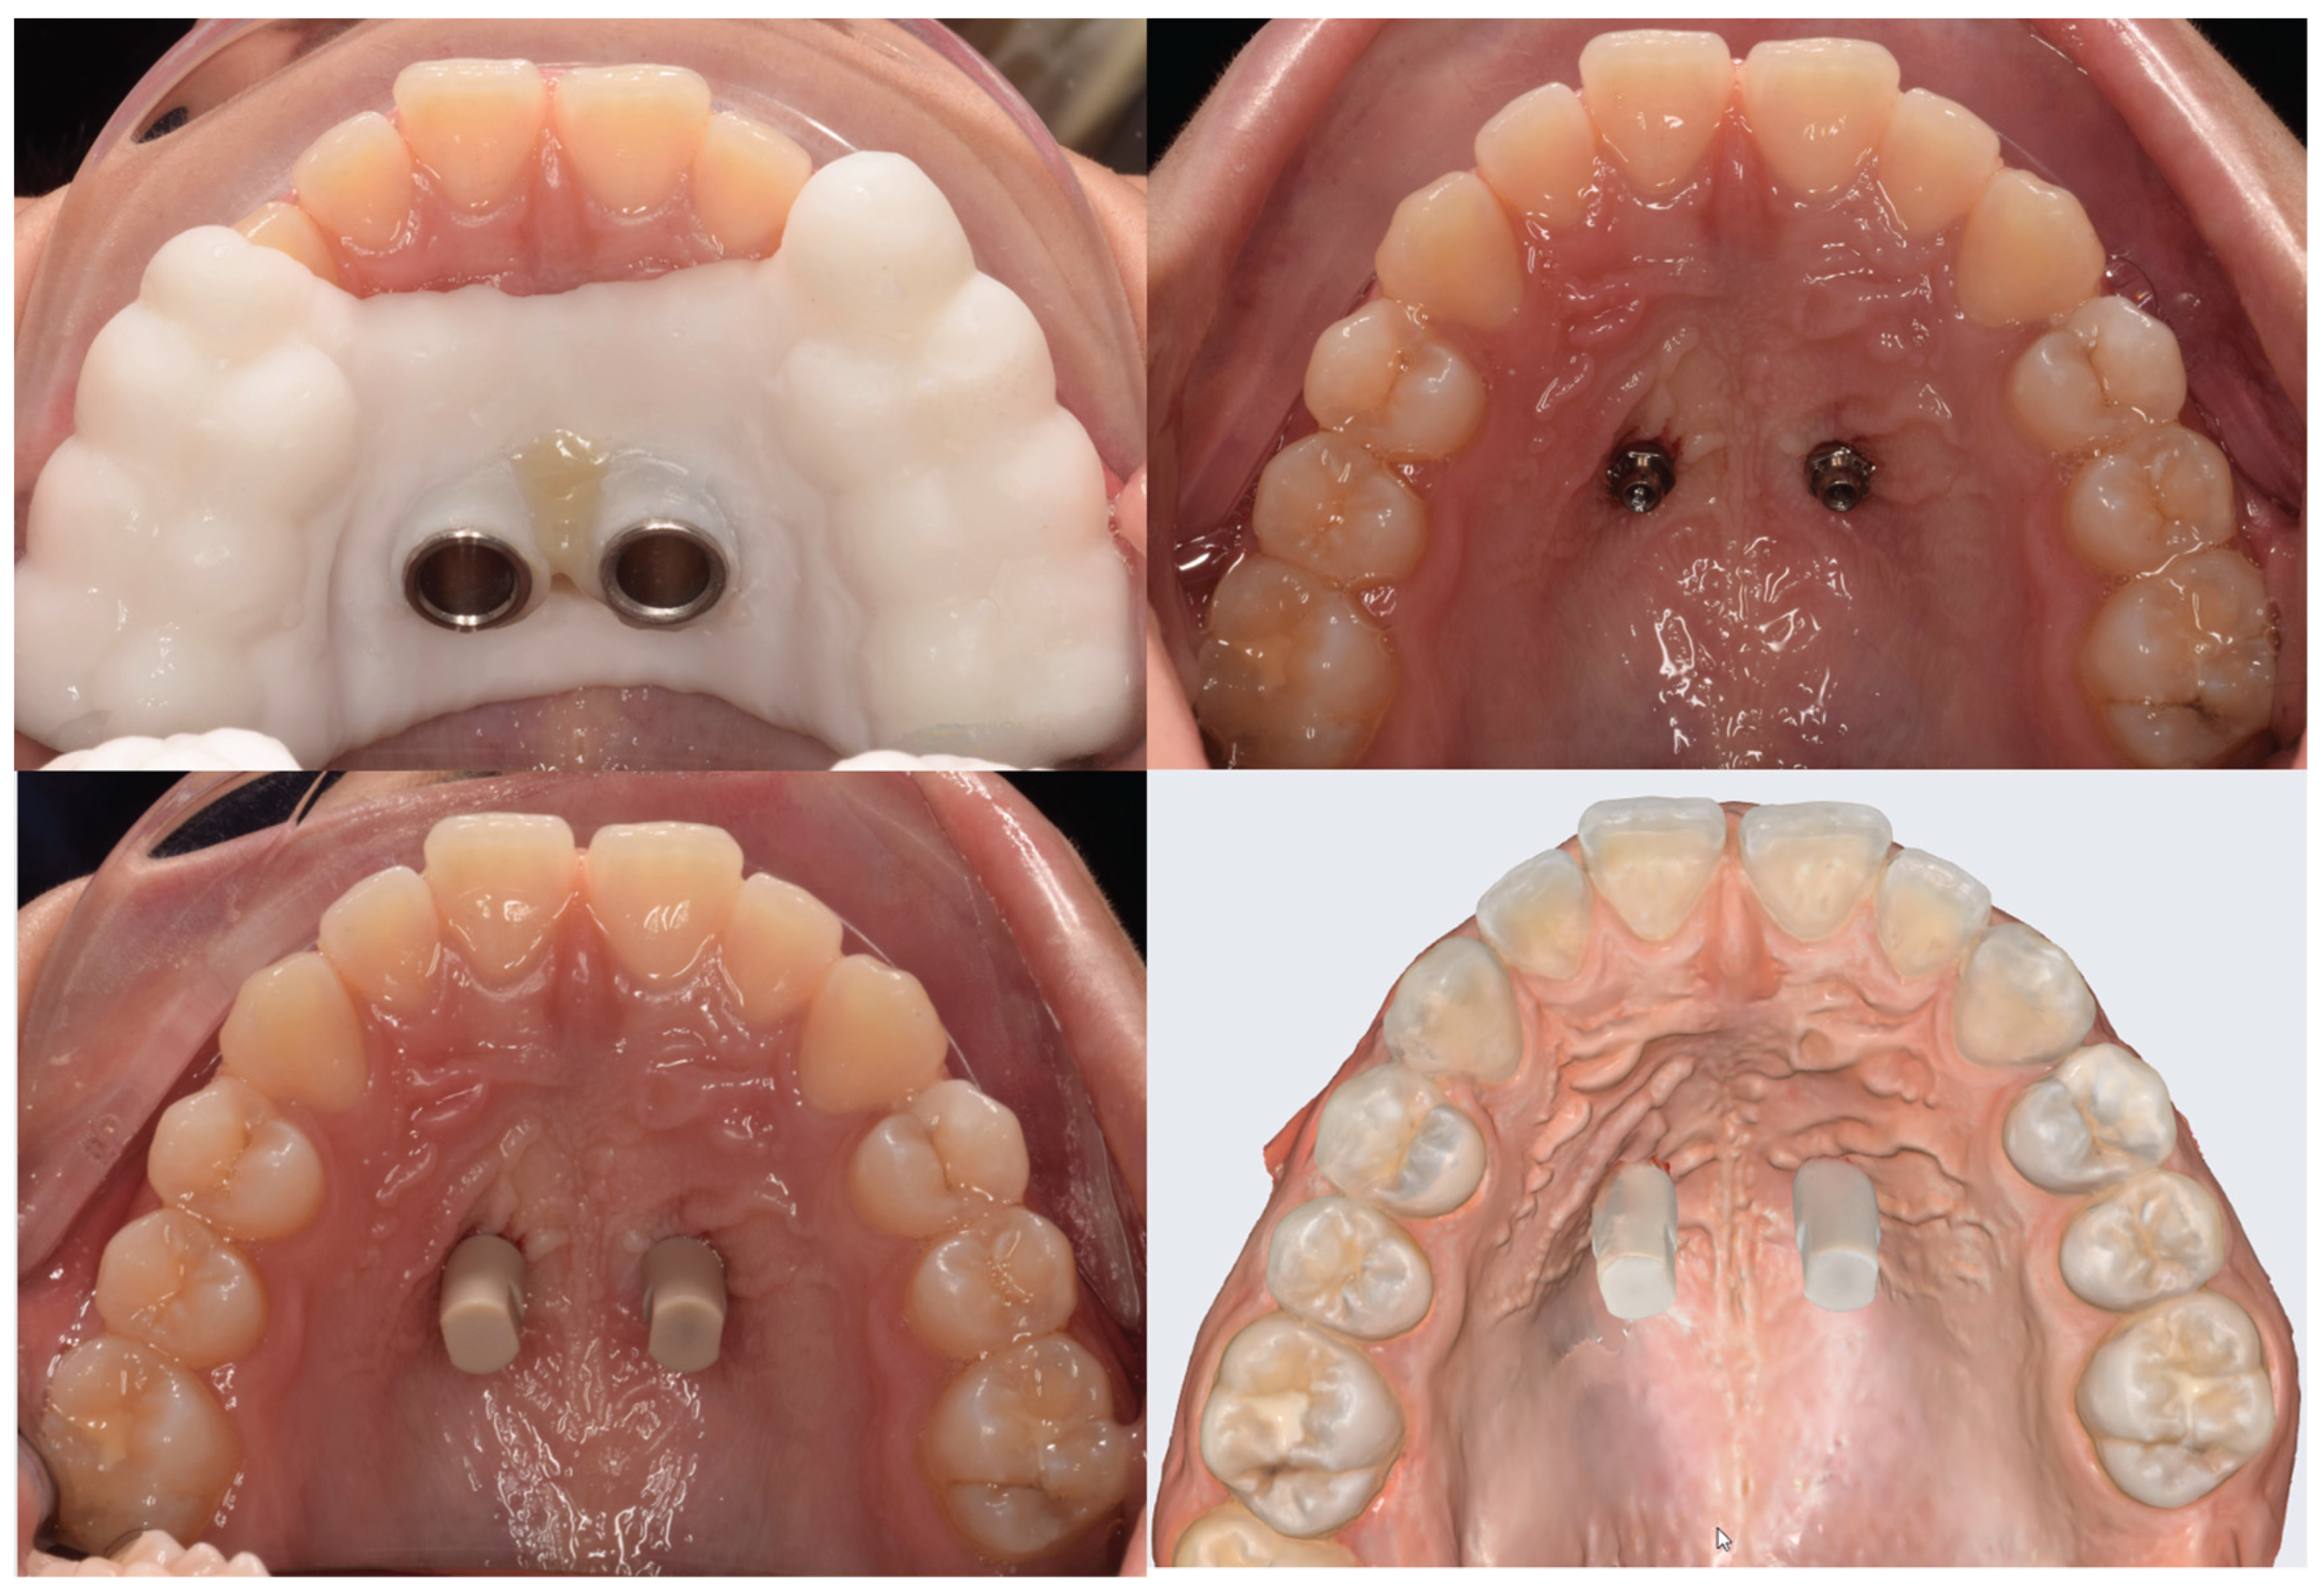

Once the orthodontic miniscrews Regular Plus Konic (HDC, Thiene, VI, | Italy) were inserted, two specific scanbodies were coupled with the two miniscrews and their position and inclination were registered by performing a new intra-oral scan with the intra-oral scanner.

This scan was used to orientate two virtual analogues of the miniscrew. These two analogues were superimposed, using BluSkyPlan Software, to the virtual analogues placed in the corresponding planned miniscrew position.

Figure 2. A- testing of the template, B-miniscrew inserted, C- Analogous application, D- Intraoral scan with analogs inserted.

Figure 3. A- testing of the template, B-miniscrew inserted, C- Analogous application, D- Intraoral scan with analogs inserted.